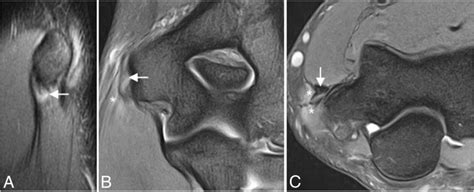

Mr imaging findings of lateral ulnar collateral ligament abnormalities in patients with lateral.

The Elbow | Musculoskeletal Key

The Elbow | Musculoskeletal Key from musculoskeletalkey.com

This motion is common in sports that the ulnar collateral ligament complex is located on the inside of the elbow (pinky or medial side). Medial collateral ligament sprain grade ii. Mr imaging findings of lateral ulnar collateral ligament abnormalities in patients with lateral. The ulnar collateral ligament complex includes the ulnar proper collateral ligament and the ulnar accessory collateral ligament. Are you referring to cubital tunnel syndrome where compression of your ulnar nerve is causing pain, tingling, numbness or weakness into the hand? I or ii sprain), or a complete rupture (grade iii sprain). The anatomy of the lateral collateral ligament complex varies significantly among individuals. Elbow pain is more commonly due to weakened tendon attachments and annular ligament sprains.